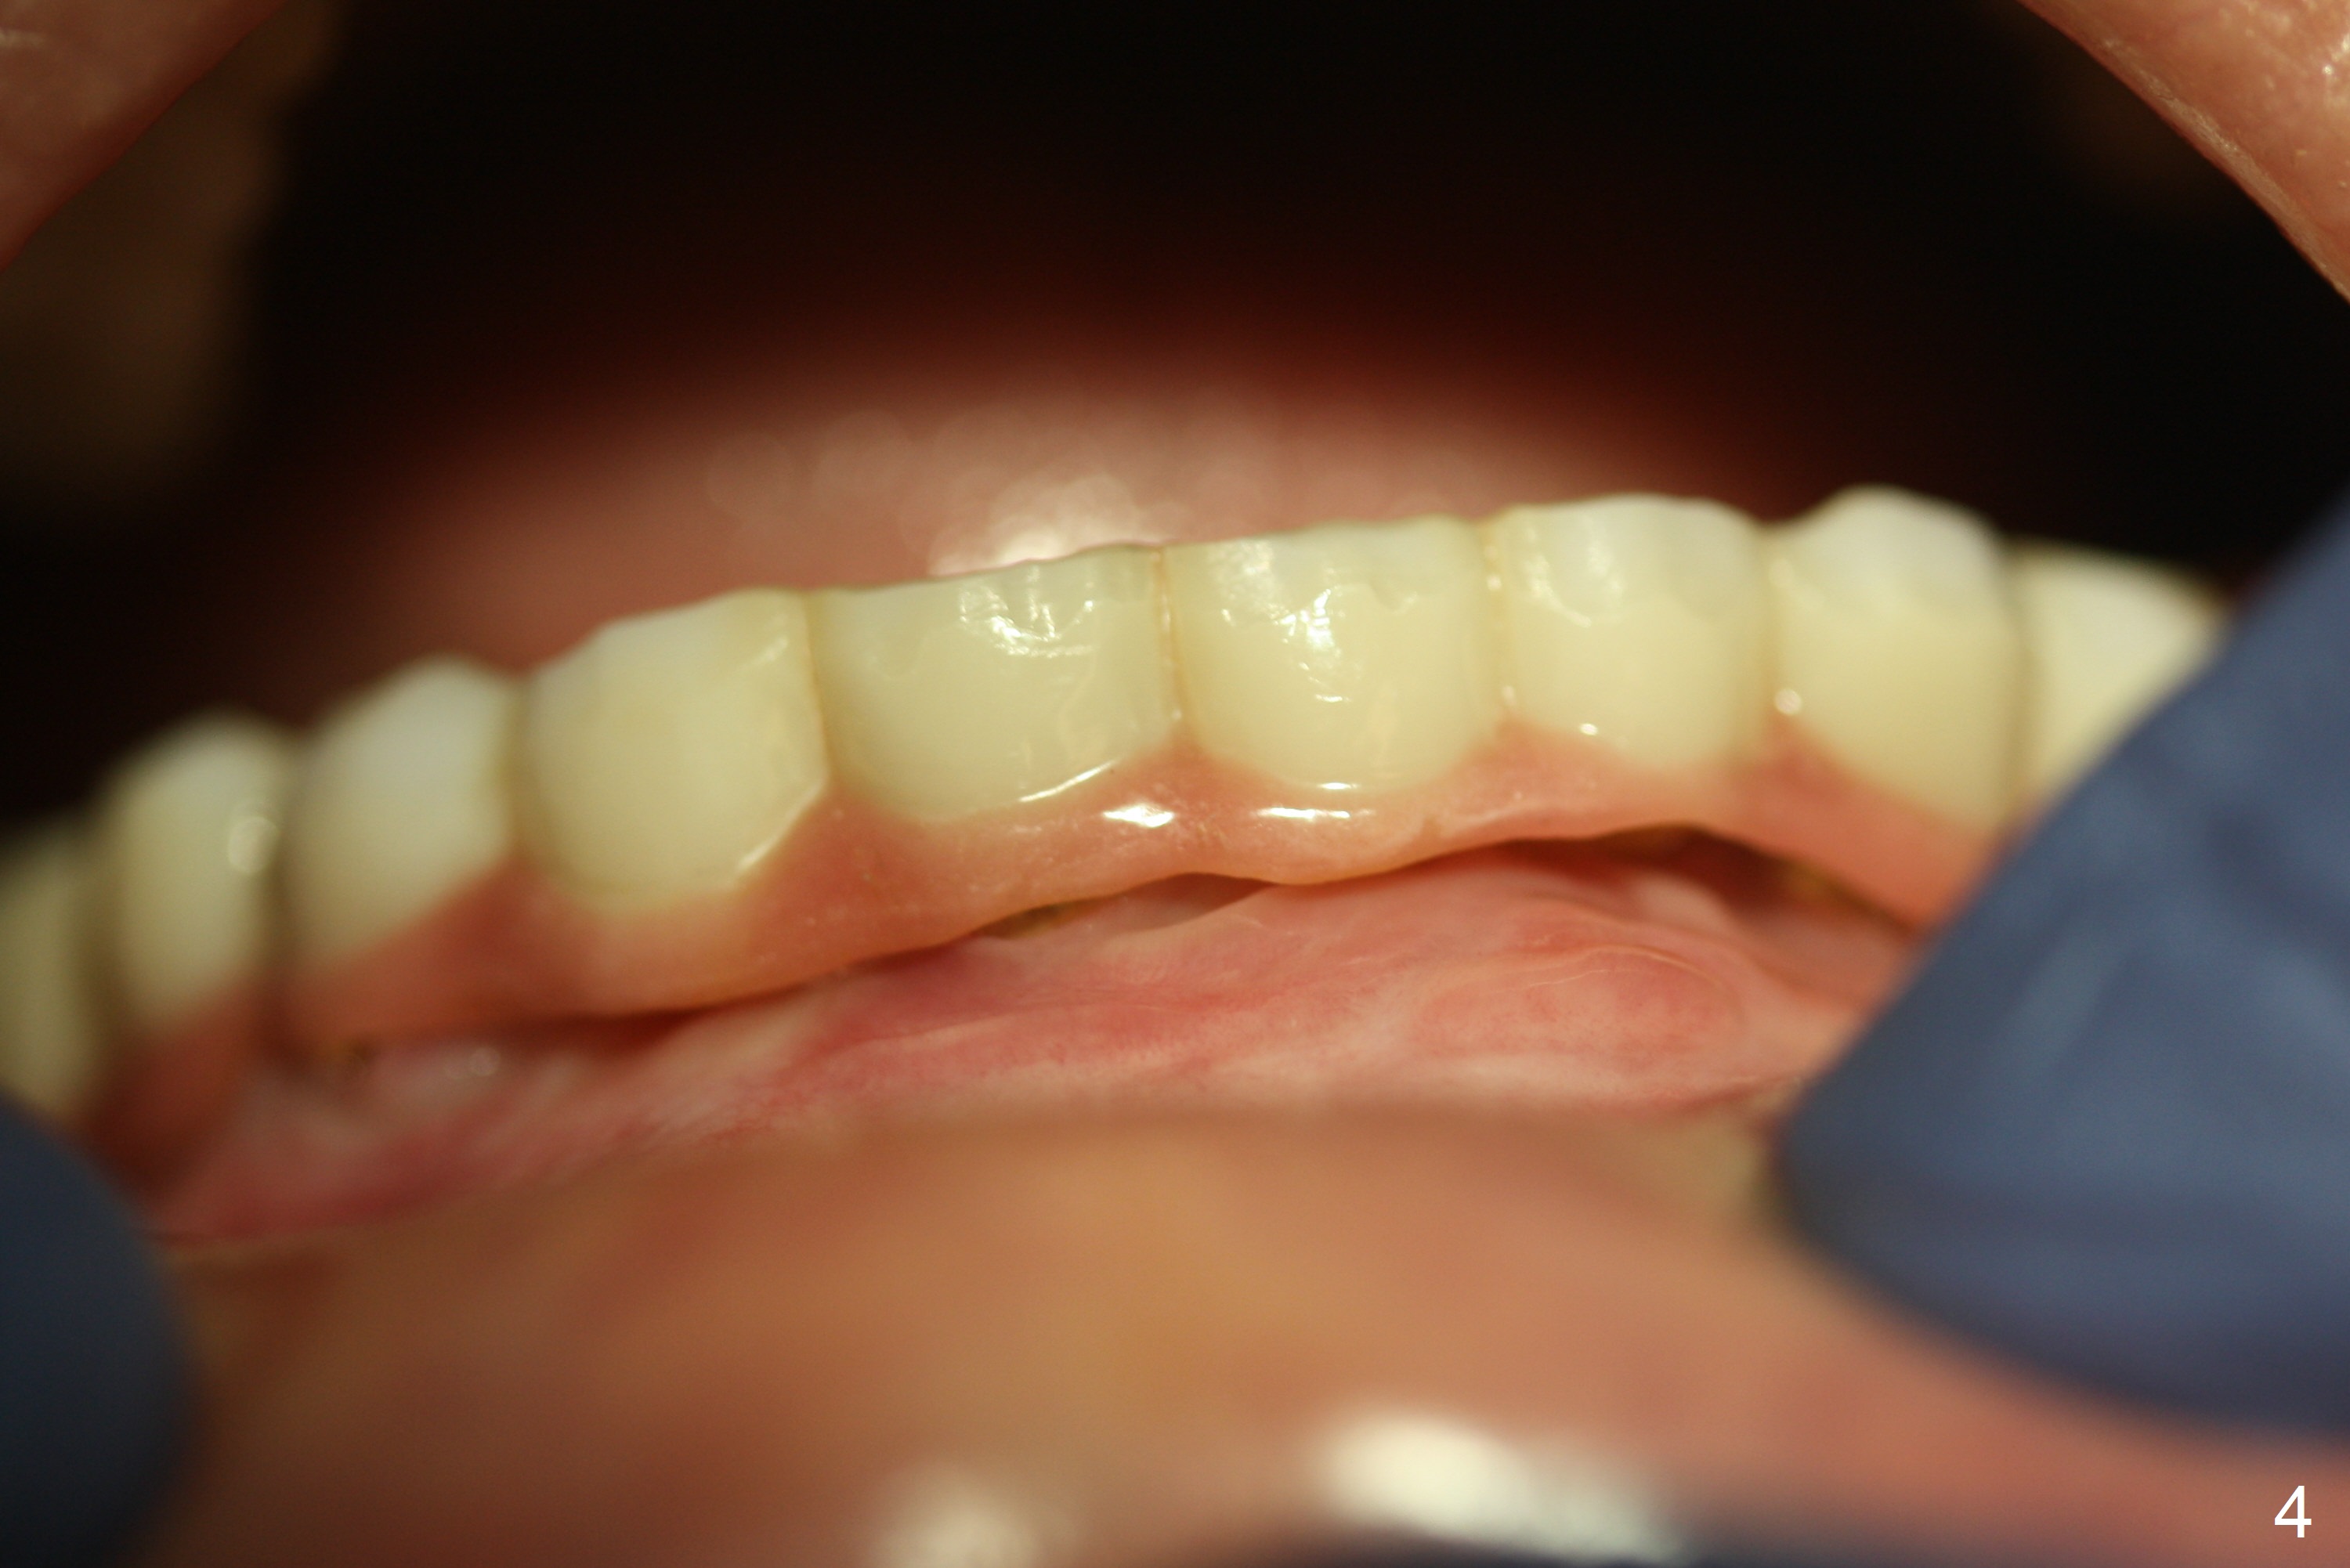

A 56-year-old woman with atrophic jaws requests redoing lower implant restoration (in function 1 year) for cosmetic reason and placing an implant at #19 (because she could not masticate on the left). Note the discrepancy between CR and CO (Fig.1,2). There is gingival hypertrophy at #31 (Fig.3), while the anterior restoration looks short with gingival recession (Fig.4). The patient is pleased instantly when lower anterior provisional is fabricated (Fig.5-7).